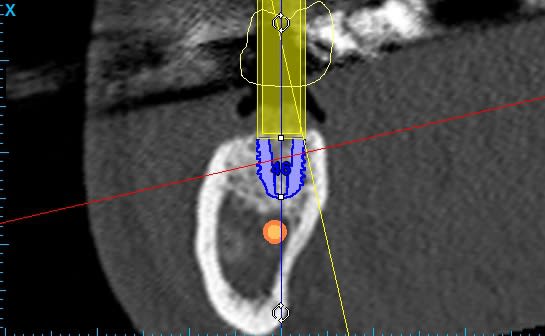

Sur la simulation que je joins, j'ai placé 2 implants 5.2 x 6.5 pour 36 et 46 en unitaire.

"quelle distance as tu entre l'implant et le NAI?"

> 2 mm. Je ne peux pas aller plus bas.